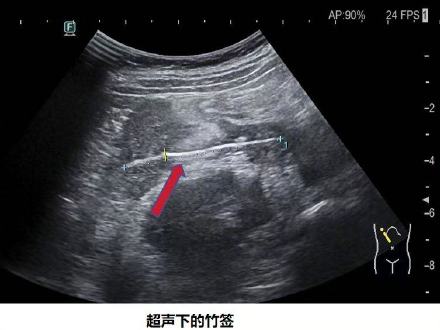

3月9日,@上游新闻 记者从重庆医科大学附属儿童医院获悉,该院近日接诊了一名持续腹痛的男孩,在男孩腹中发现了一根长约6厘米的竹签,经家长与男孩回忆,应该是他吃鸡柳时误食,检查时,竹签已经刺穿男孩十二指肠并刺破男孩肝脏,医生随后手术取出竹签。

重医附属儿童医院超声科主任汪朝霞介绍,该院已经接诊过多例儿童误食异物造成消化道伤害的案例,水宝宝、磁力珠、鱼刺、牙签、硬币、纽扣电池、枣核等都曾在孩子腹中被发现。

她提醒,家长日常要注意预防孩子吞食异物,异物易引起肠梗阻及损伤肠壁,严重的还会引发肠穿孔、腹膜炎、腹腔脓肿、血管破裂等严重后果,甚至危及生命。 (上游新闻记者 石亨 重医附属儿童医院供图)